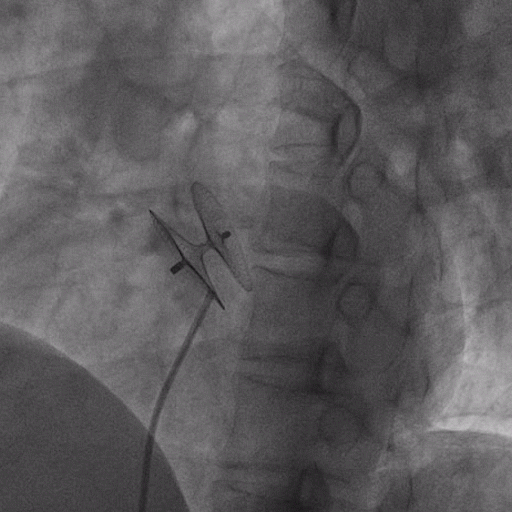

在獲得患者同意后,1月12日,尚福軍主任為患者進(jìn)行了PFO封堵術(shù)。術(shù)中造影可見封堵器殘余漏,尚福軍主任用精湛的技藝,順利通過封堵器殘余漏裂縫,將右心導(dǎo)管從右房送入左房,且順利到達(dá)肺靜脈;遂行卵圓孔未閉封堵術(shù)后殘余漏再次封堵;且完美釋放PFO封堵器,可見兩封堵器呈“馬蹄蓮”狀,再次術(shù)中造影未見殘余漏。